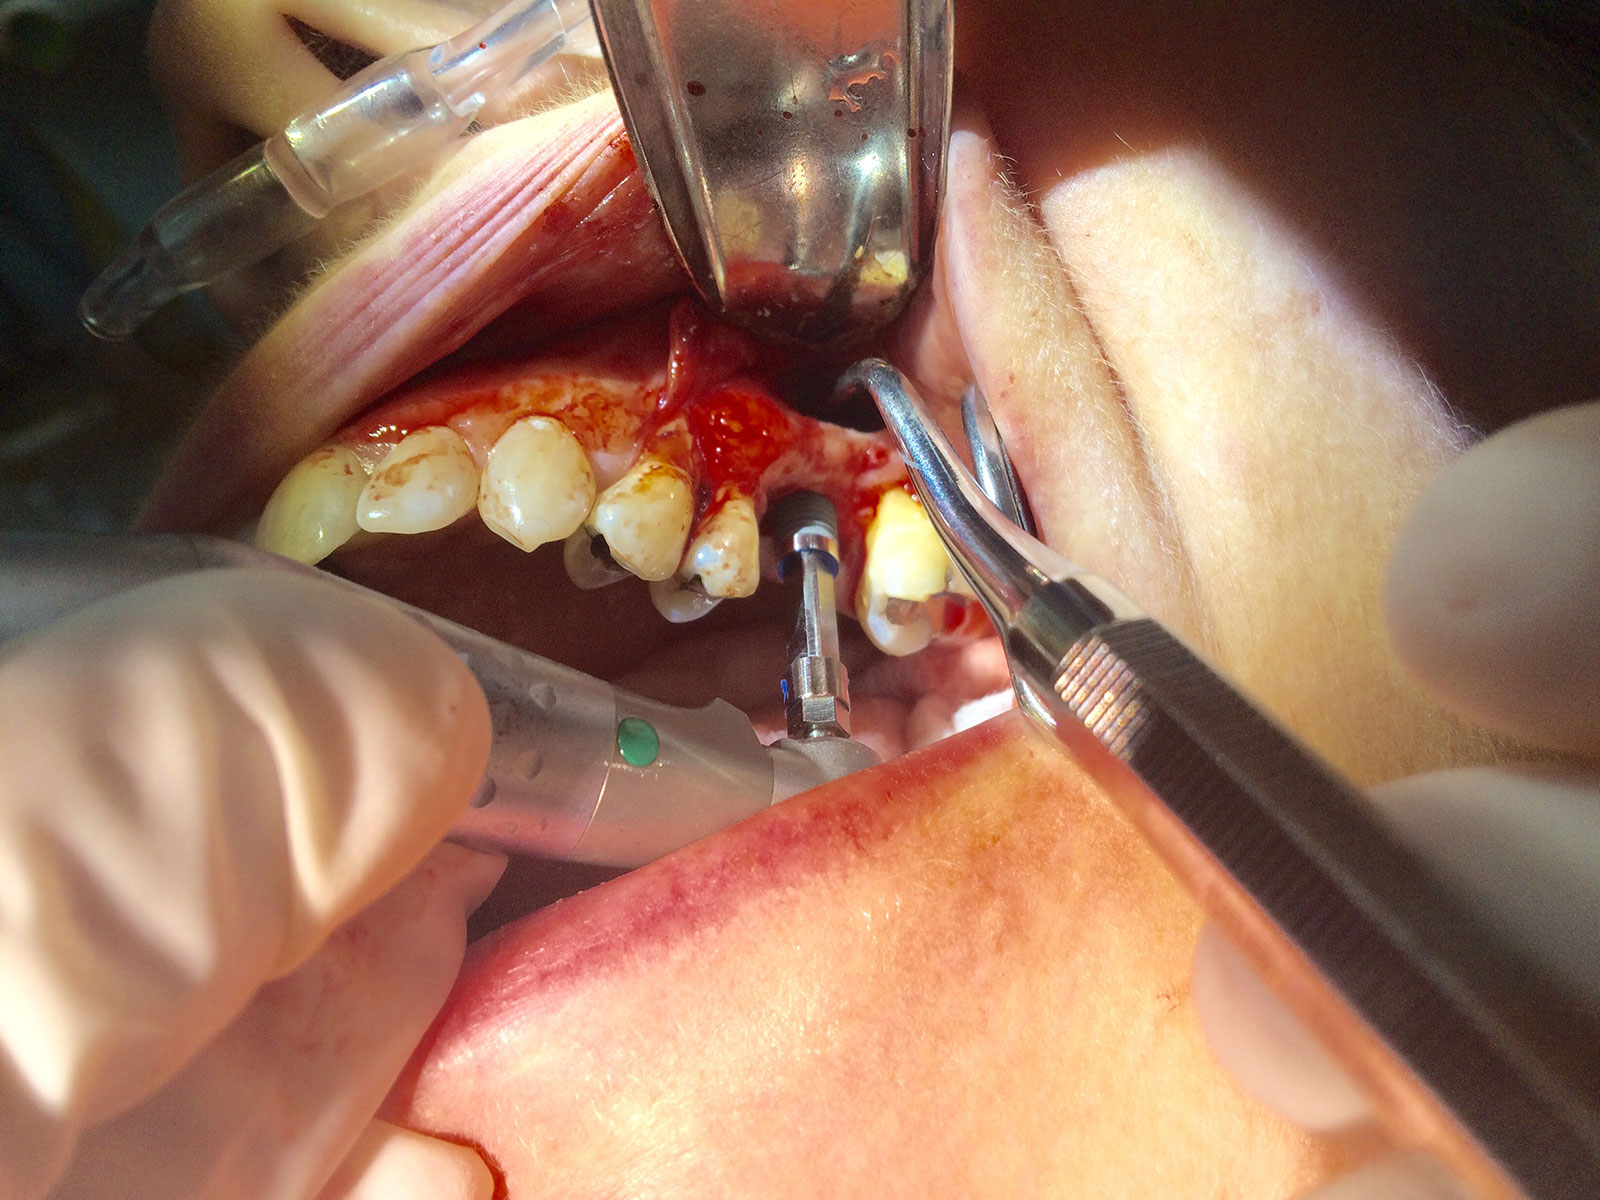

Sinus Grafting Procedures

A sinus grafting procedure, also known as a sinus augmentation, is for patients who have insufficient natural bone in the areas where dental implants are needed. They are long lasting, strong and sturdy, and fit and function like natural teeth. The procedure involves adding bone, either your own natural bone from another part of the body, from a donor or made of processed or synthetic bone material, and placing it below the sinus so that the implants can be placed. After the bone has healed and developed, usually around four to 12 months, the dental implants can be placed.

The photos on this website are from real surgeries performed by Dr. Ulloa. Due to the

graphic nature of the images and content, viewer discretion is advised.

Click to enlarge images